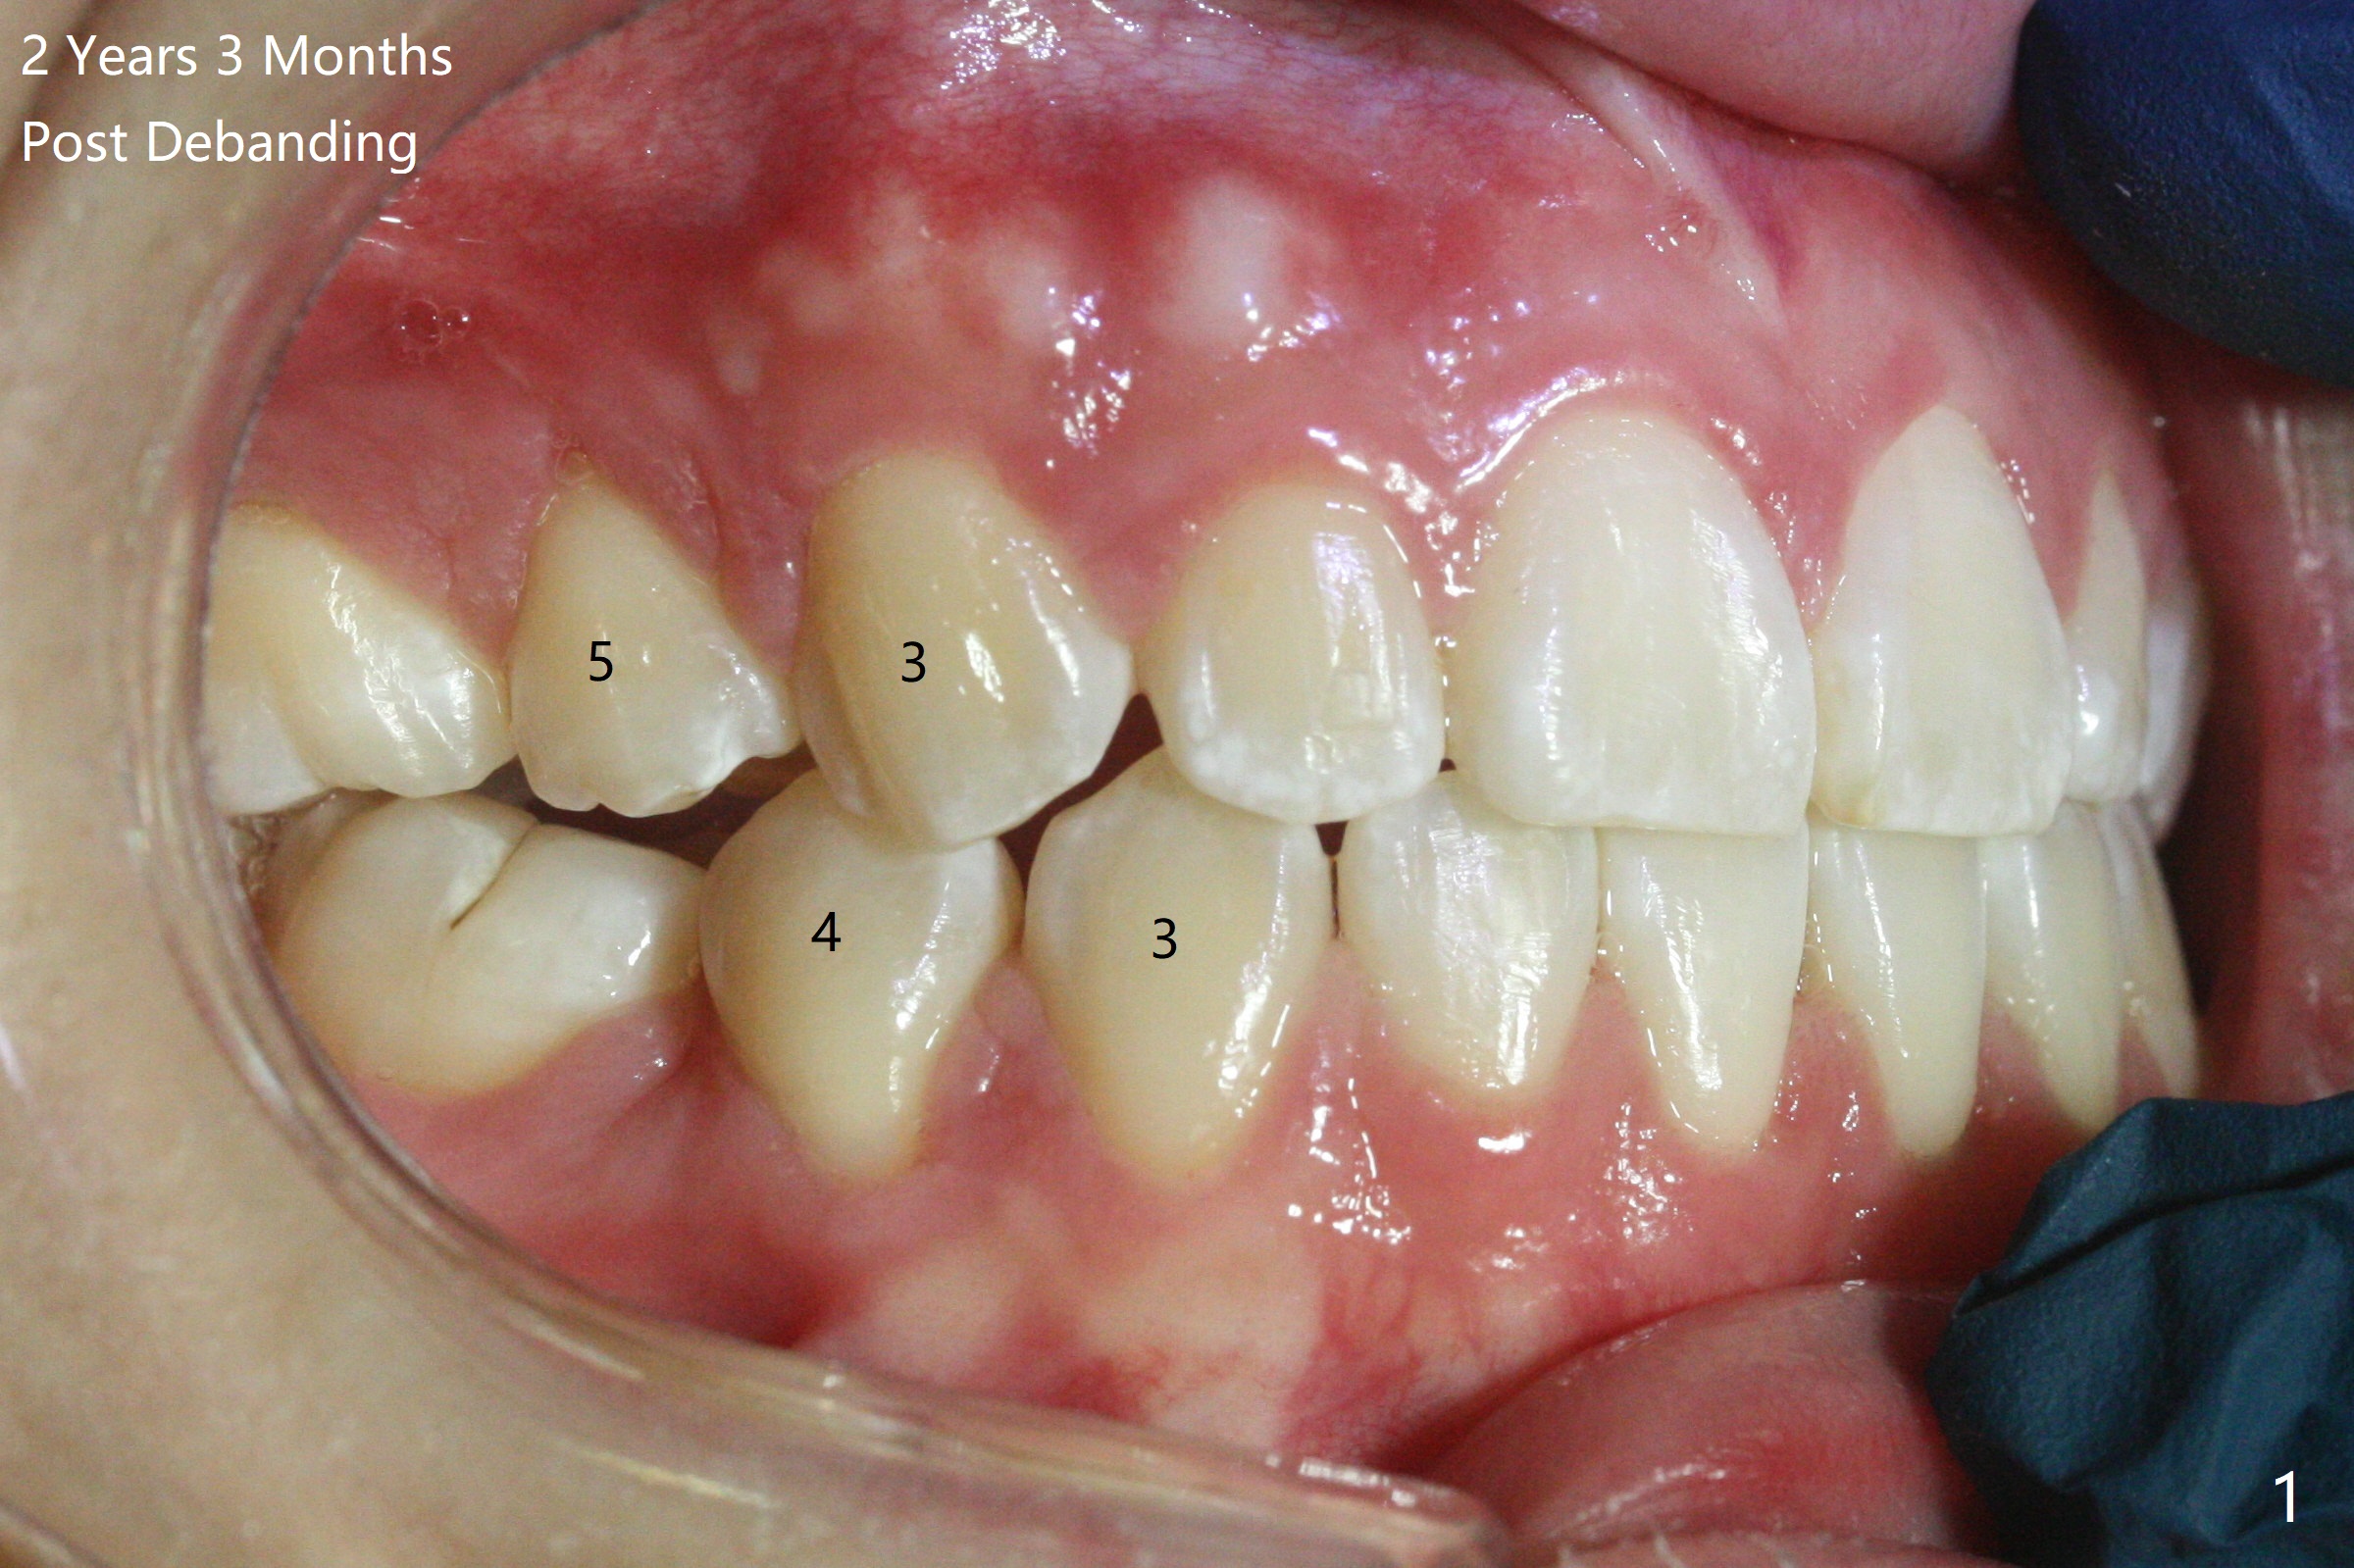

Follow Up: 2 Years 3 Months Post Debanding with UL3, LL5 Congenital Missing

A 16-year-old woman